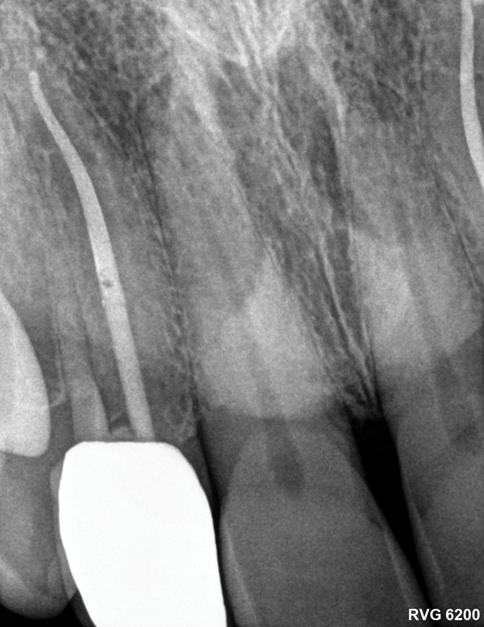

Other common risks associated with post placement include the occurrence of root fracture, perforation, and apical leakage as well as the development of caries (Figure 1 through Figure 3).9 How the post space is prepared significantly affects the ability of the root canal filling material to create a seal.11 Apical leakage increases in correlation with the amount of gutta percha removed from an endodontically treated tooth, increasing the risk of reinfection.11 The risks of fracture and perforation must also be seriously considered. After the performance of endodontic treatment alone, furcation-side dentin thickness in the distal roots of mandibular molars has been shown to be less than 1 mm in more than 80% of teeth.12 After preparation of the post space, the remaining dentin thickness in the buccal roots of premolars has been shown to be often less than 1 mm.13 The remaining thickness of the root dentin after endodontic and post placement procedures is the factor most highly correlated with future resistance against root fractures.13 These anatomic studies underscore the need for judicious preparation, and the risks of post placement underscore the need for careful case selection.

(1.) A radiograph of a root fracture associated with a threaded post, cone-beam computed tomography views of a perforation associated with a post, and a radiograph demonstrating evidence of apical leakage associated with posts, respectively.

Figure 1